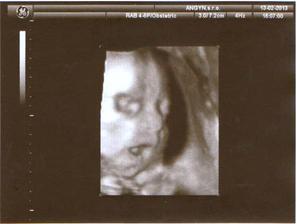

13.3.2013 - 28tt. návšteva poradne, glukózový test úspešne za nami, USG, 1160 gramov, 3D meúspešné kedže sa nám stále schovávala